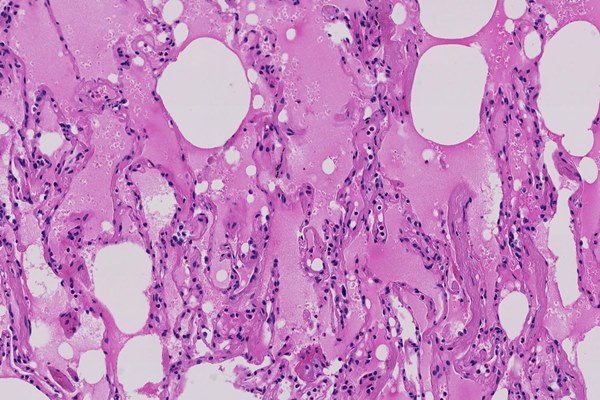

Ảnh chụp tuyến phổi của bệnh nhân đến từ Vũ Hán, cho thấy phế nang chứa đầy chất lỏng màu hồng, sự thay đổi sớm nhất trong phổi của bệnh nhân. Ảnh: Shu-Yuan Xiao.

Sự sưng tấy và dòng lưu thông oxy bị suy yếu có thể khiến những khu vực đó trong phổi chứa đầy chất lỏng, mủ và tế bào chết. Viêm phổi, một dạng nhiễm trùng, có thể xảy ra.

Một số người khó thở đến mức cần phải đặt máy thở. Trong những trường hợp xấu nhất, được gọi là Hội chứng Suy hô hấp Cấp tính, phổi chứa quá nhiều chất lỏng mà không có sự hỗ trợ hô hấp nào có thể giúp đỡ, và bệnh nhân chết.